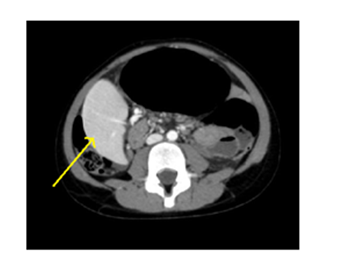

A five years old girl was taken to our emergency department with a history of few hours of acute abdominal pain in the upper quadrants and non biliary vomiting, followed by retching. The patient was afebrile, with a huge distended abdomen, without tenderness. The rest of the physical examination was unremarkable. A nasogastric tube was passed with some difficulty, a venous access was secured and blood tests were taken: WBC were 12.050U/uL, RCP was 8,8mg/L, pancreatic amylase were elevated at 430U/L. Serum electrolytes, liver and renal function, haemostasis were normal. An abdominal ultrasound (US) revealed a spleen localized in the right flank, below the liver and an abdominal computed tomography (CT) scan was performed (Figures 1-2). The exam showed a well vascularised spleen in the right flank below the liver, a dislocation to the right of the pancreatic tail and body and a huge distended stomach with a the nasogastric tube inside. The diagnosis was gastric volvolus associated with wandering spleen and pancreatic torsion. Fluid resuscitation and antibiotic therapy were started. The girl spontaneously lied on the left flank as her preferred decubitus and after a while the spleen was palpated not in the right flank but in mesogastrium. She was taken to the operatory theatre as soon as fluid resuscitation was secured an emergency and an open laparotomy was performed. A gastric mesenteroaxial volvolus was found associated to uncomplete torsion of the spleen and pancreatic tail. There were no legaments of fixation between spleen and stomach, nor between spleen and kidney, nor between spleen and abdominal wall. There were no signs of severe gastric ischemia. The stomach was derotated and the spleen restored to its normal position since the tissue was completely viable. An omental patch associated to splenopexy was performed to keep the spleen in place and a diaphragmatic and anterior gastropexy was performed. The recovery was uneventful, the amylases returned to normal values within two days and the girl was discharged on postoperative day 4th. At 24months the girl is asymptomatic and a follow-up ultrasound revealed a spleen and stomach in its normal position.

Figure 1 Axial section of abdominal CT scan, yellow arrow points to the spleen in the right flank.